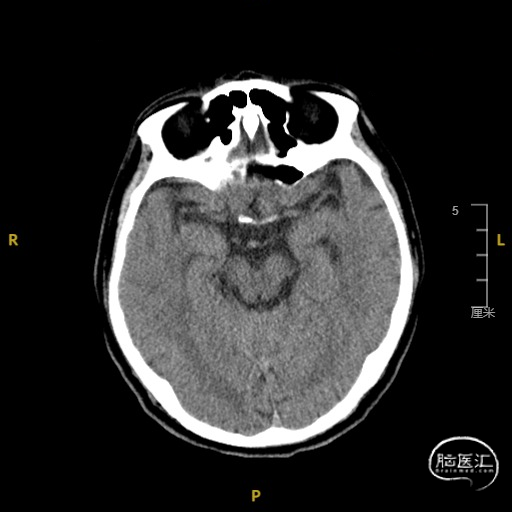

术后常规复查头CT未见明显出血。

4.0*30mm通桥白驹®球囊以6atm扩张(左图箭头),扩张完毕后多角度造影显示狭窄交前明显改善(中图箭头处),扩张完毕后支架置入(右图箭头处)。